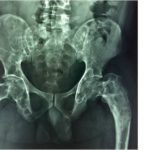

1. when a titanium hip socket/joint is used to replace the original bone…how is the blood supply, the marrow, the production of cells, then produced and;

2. how does the ‘body’ know or be aware of, the new replacements, ‘position’ ie no labrum, no bone to body relationship? I curious.